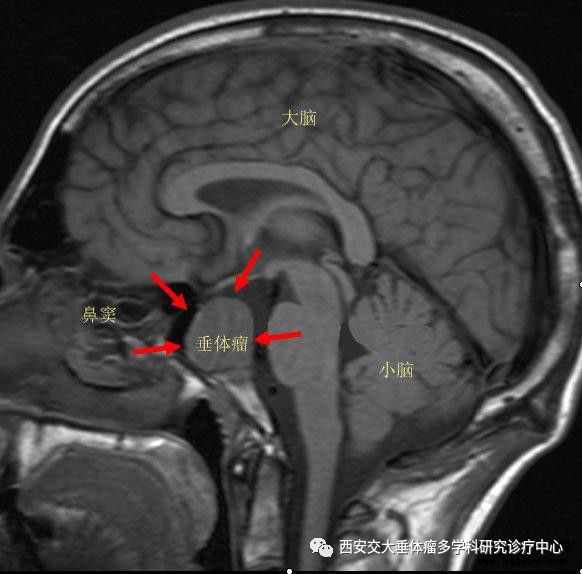

其实发生"蝶鞍区"的疾病在我们医学上专业叫作"鞍区占位",虽然鞍区

蝶鞍区解剖及疾病的影像解剖